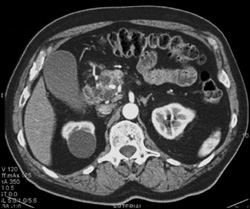

CASE NUMBER 673

Multiple Intraductal Papillary Mucinous Neoplasms (IPMNs)